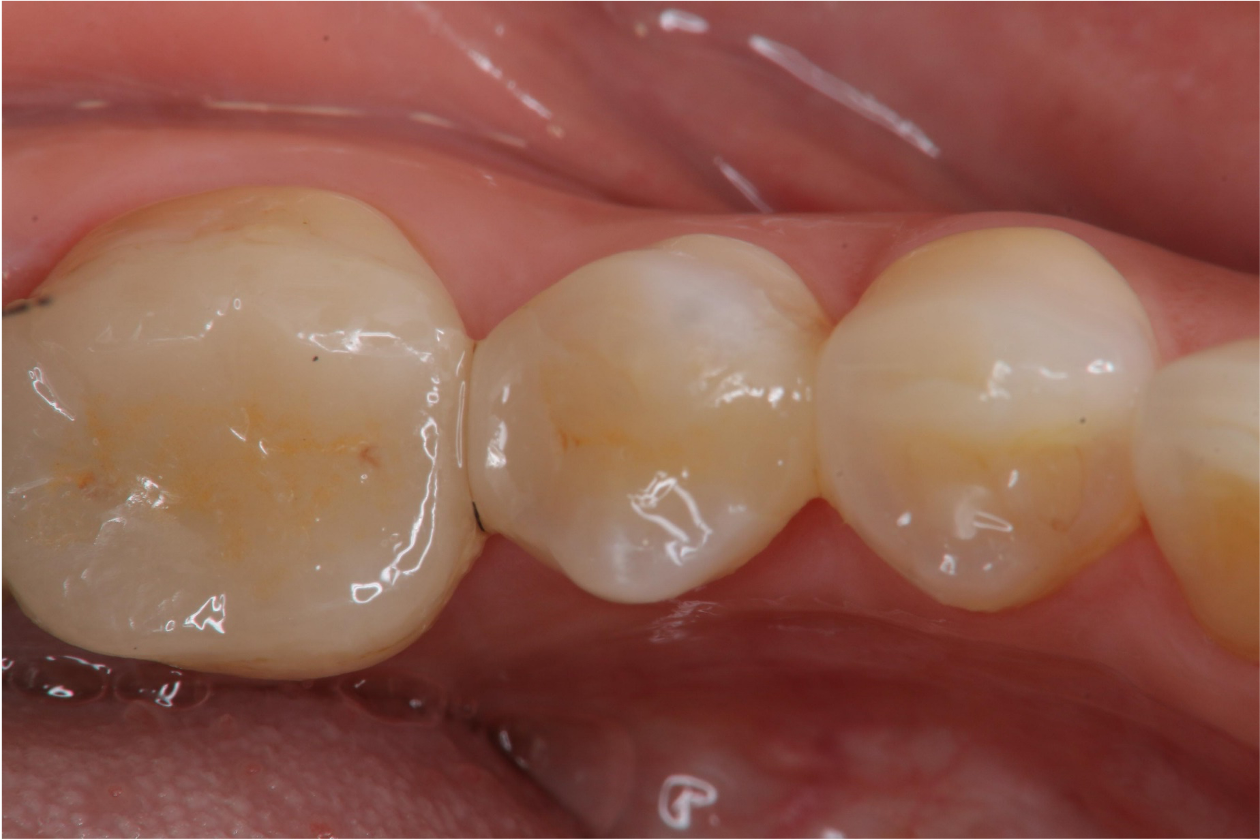

1週後口內照